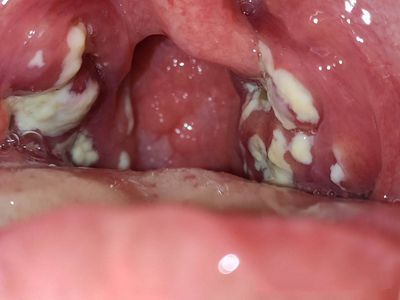

化脓性扁桃体炎喉咙两侧有白膜覆盖图

化脓性扁桃体炎咽部两侧扁桃体被黄白色假膜覆盖,形似白斑,假膜容易被擦去,假膜下的创面潮红,不易出血,伴有明显咽痛,吞咽时疼痛更加明显。